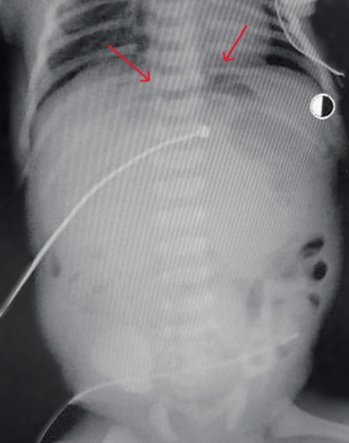

At 37 hours of life, with a diagnosis of intestinal obstruction, perforation of a hollow organ, he was transferred for surgical care to the neonatal intensive care unit of the regional children's clinical hospital in severe condition on mechanical ventilation. Abdominal X-rays revealed the "sickle" sign characteristic of pneumoperitoneum (Fig. 4).

Fig. 4: Abdominal X-ray showing the characteristic "sickle" sign of pneumoperitoneum